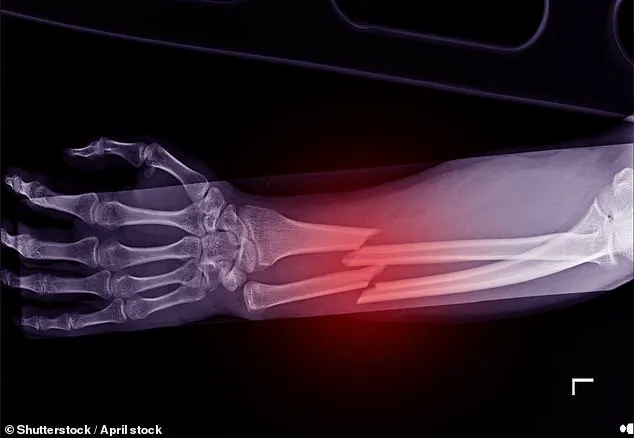

The introduction of AI into healthcare diagnostics holds significant promise, particularly in identifying ‘hard-to-spot’ fractures—a common issue in emergency departments due to a shortage of radiologists and radiographers.

The National Institute for Health and Care Excellence (NICE) has reported that missed fractures are among the most frequent errors in A&E settings.

The health service’s spending watchdog recently approved four AI programs designed to reduce undiagnosed bone breaks in hospitals.

These technologies include TechCare Alert, Rayvolve, BoneView, and RBfracture, with an estimated improvement rate of about 15 per cent for fracture detection accuracy.

While doctors will continue assessing scans manually, the new AI technology aims to identify smaller fractures that might be overlooked.

This advancement could prove crucial in preventing further injuries among patients who have suffered missed fractures while also accelerating their recovery process.

Approximately 200,000 people are admitted annually with a fracture; hip, ankle, and hand fractures being the most prevalent.

Individuals diagnosed with osteoporosis—an age-related condition leading to bone thinning—are particularly prone to such incidents.

The AI scanning technology is developed through extensive training of machine learning algorithms on thousands of images of bones until they can recognize signs of fractures accurately.